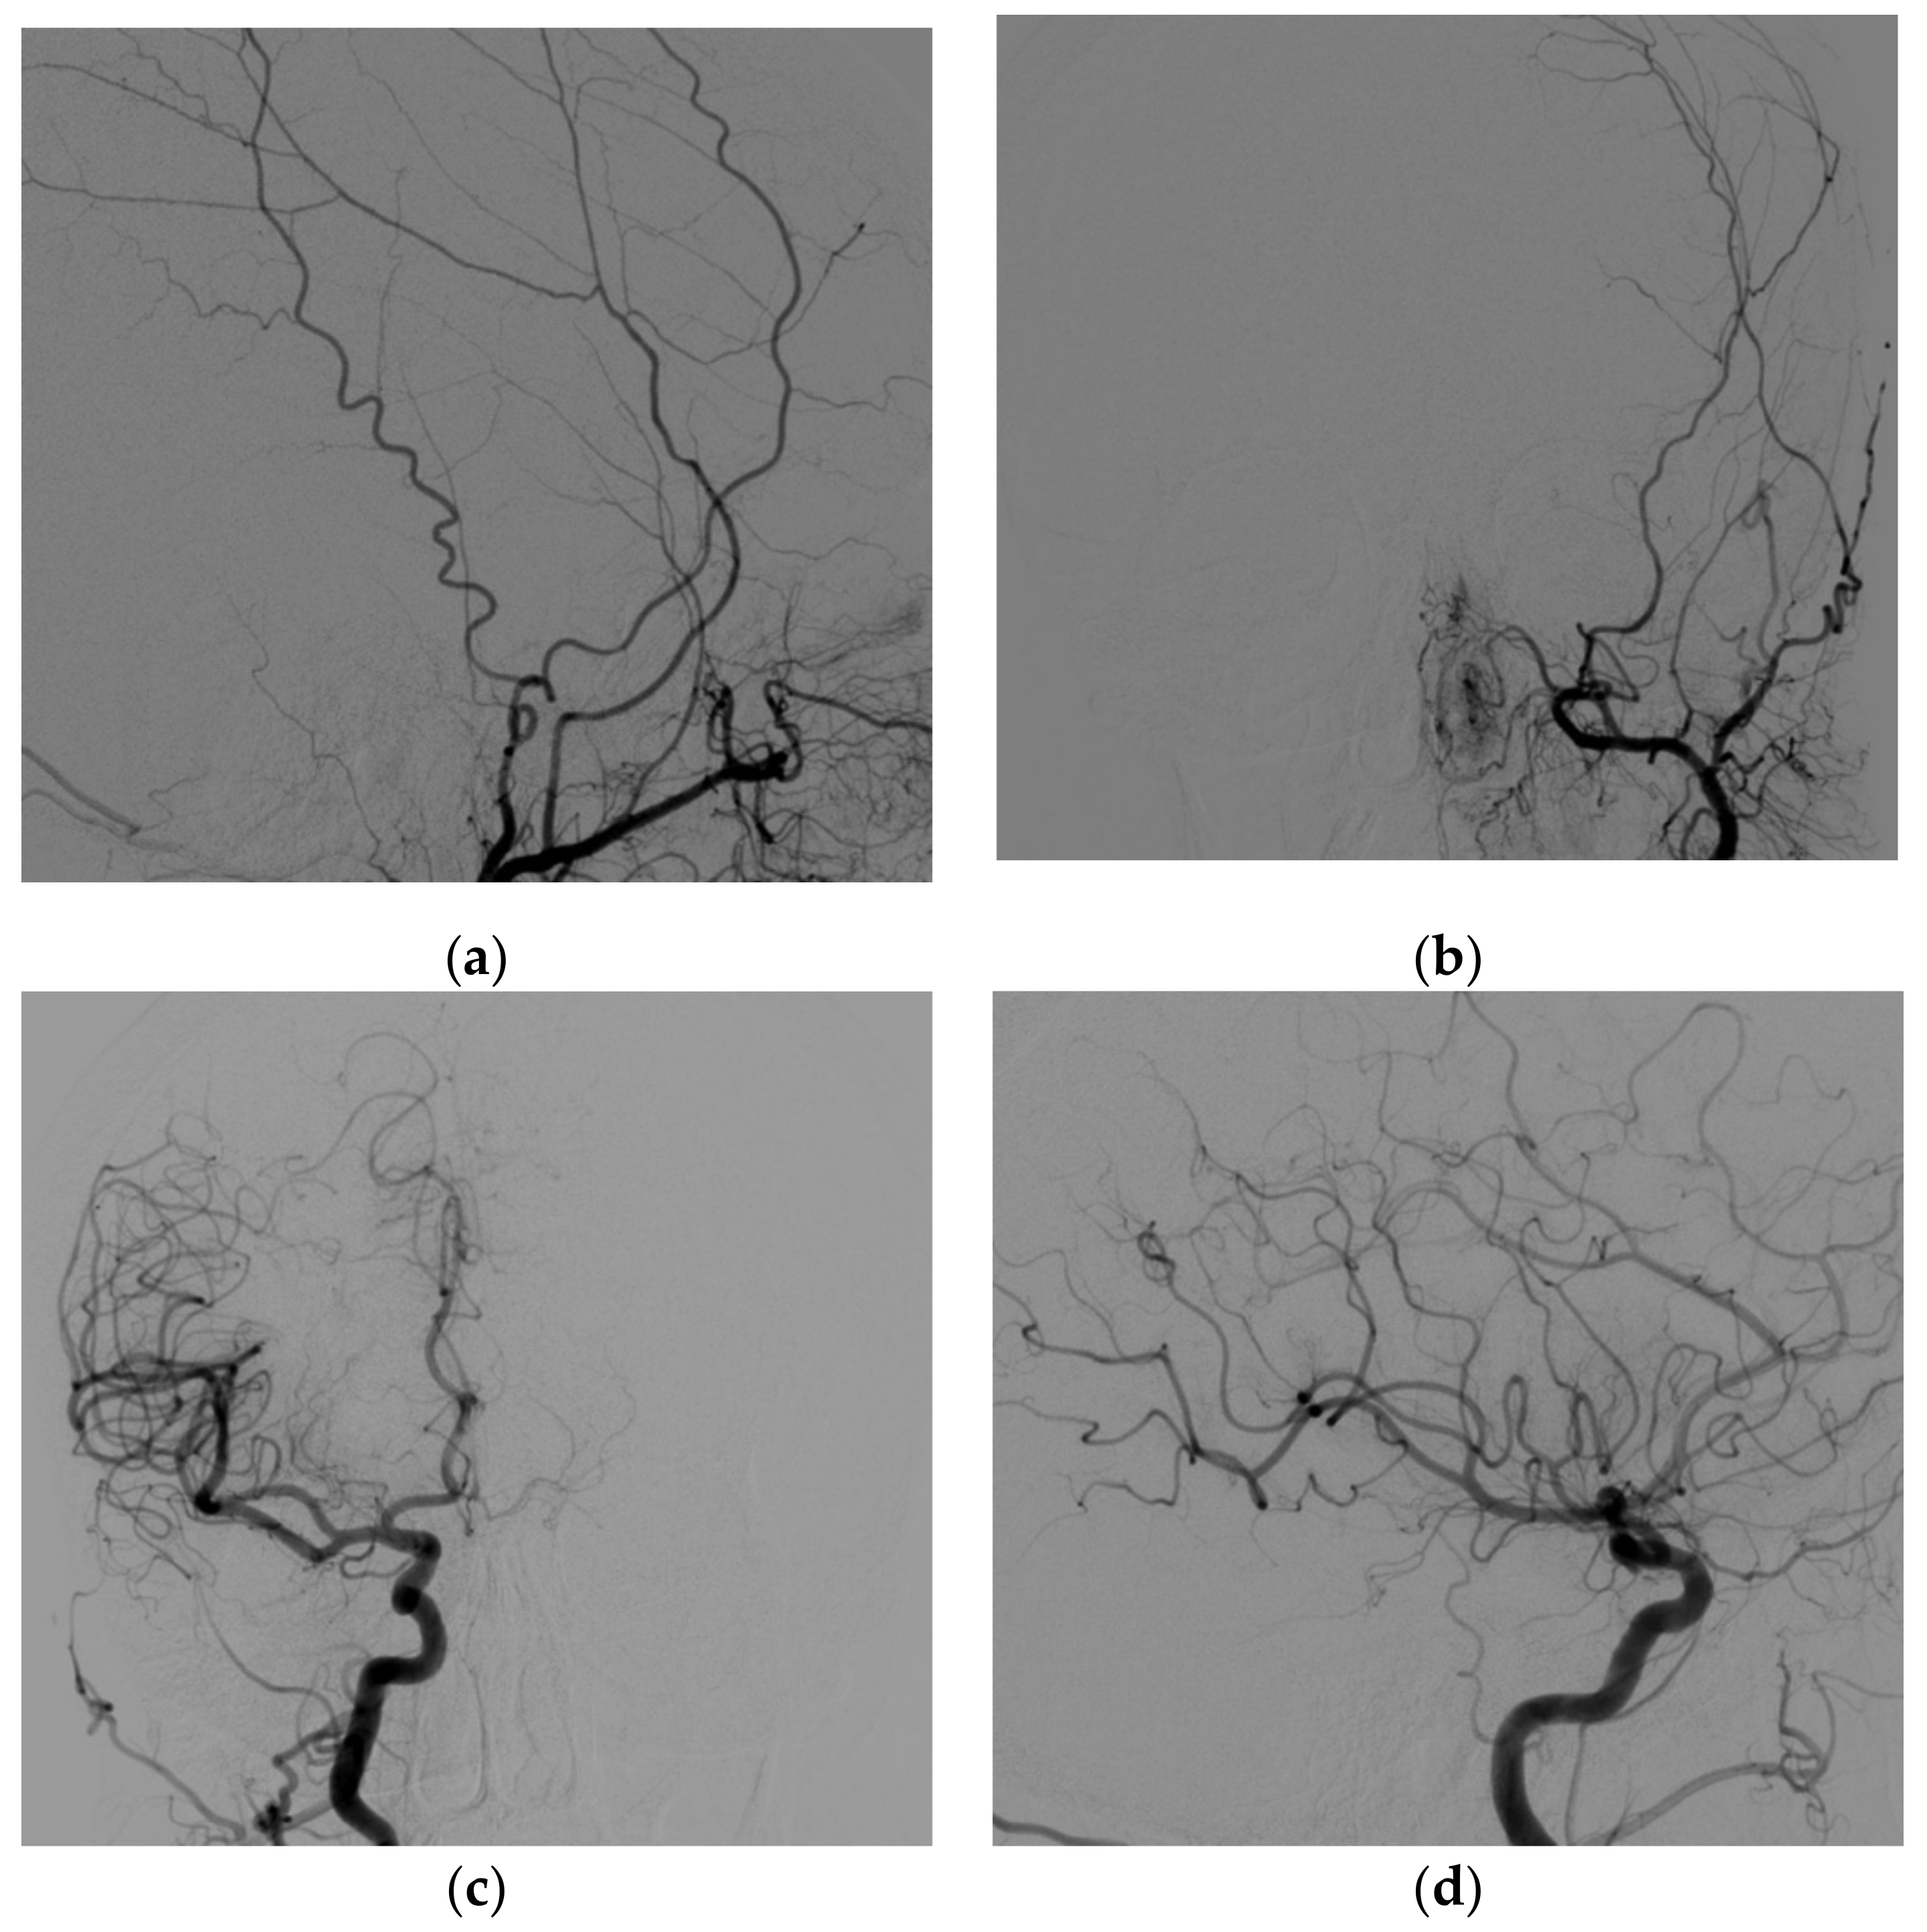

The follow-up CT angio examinations showed that the venous pouch of the CS-DAVF progressively decreased in size (Figure 5a–c), and at the final DSA after the end of the cycle of corticosteroid therapy (performed 7 months after discharge), it was completely occluded (Figure 6a–d). From the clinical point of view, the proptosis regressed, and diplopia and retroorbital pain disappeared; a slight conjunctival hyperemia remains but at three years, the patient is still free of symptoms.

Figure 6. DSA at 7 months, left external carotid artery, lateral (a) and antero-posterior (b) views. right internal carotid artery antero-posterior (c) and lateral (d) view. The DSA shows complete resolution of the dural fistula.